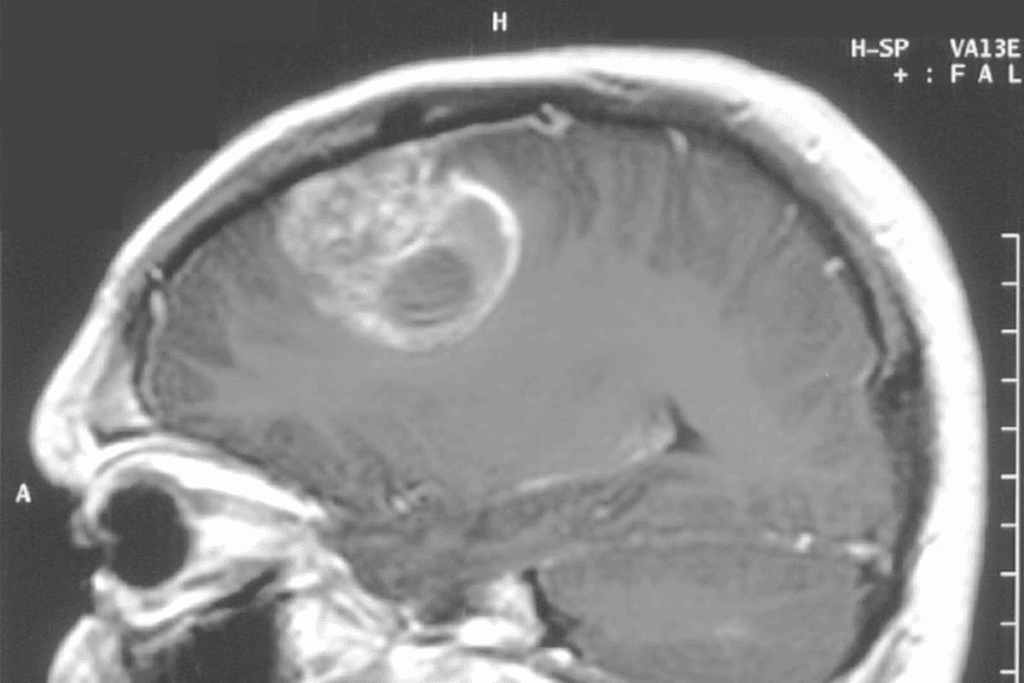

Imaging Characteristics of DIPG

Diagnosing DIPG uses advanced imaging like MRI. DIPG tumors look like diffuse, infiltrative lesions in the pons. They often spread into the surrounding brainstem structures.

This makes it hard to plan surgery. MRI sequences like diffusion-weighted imaging and MR spectroscopy help. But, DIPG’s growth into the brainstem tissue is a big challenge for surgery.